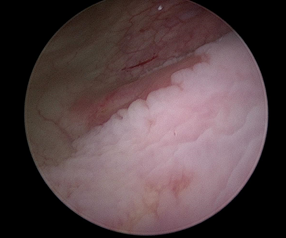

This is a 38-year-old female patient, with no medical history of importance. Gynecological and obstetric history: menarche at 12 years of age, gestation 1, cesarean section 1 in 2020, she has a pap smear in April 2023 with negative report of malignancy. Her surgical history includes laparotomy with right oophorectomy in September 2023 due to the presence of endometrioma. Her condition began 6 months prior to her evaluation when she presented abnormal uterine bleeding due to an increase in the number of periods, as well as more frequent cycles accompanied by dysmenorrhea, she denies any other added symptomatology. On arrival, a complete physical examination was performed, where the vaginal examination revealed a barrel-shaped cervix, speculoscopy was performed and a verrucous lesion was found, hypervascularized at that time, a biopsy was performed which reported endocervical mucosa with moderate chronic inflammation and papillary, mild vascular congestion, compatible with endocervical polyp. No neoplastic cells were identified. Medical treatment is started with analgesics without improvement of the picture and an MRI is requested with mapping for endometriosis in which it is reported: Uterus in anteversion, globular appearance, increased in size with dimensions of 10.8 x 7.6 x 7.2 cm with an image on the posterior wall measuring 11 mm and is 100% intramural. Endometrial myometrial thickened area of 16 mm. Diffuse adenomyosis, endometrioma in left ovary of 3 cm. Nodular endometriotic implant of cystic aspect in cervical isthmus junction. For these reasons, together with the patient, it was decided to perform a total hysterectomy by laparoscopy and endometriosis resection. At the beginning of the procedure, lesions were observed (Figure 1), which macroscopically were not compatible with endometriosis, so biopsies of the lesions were taken and sent for transoperative study.

Figure 1 Laproscopic image of lesions at the level of the right costal grid, (B) Laproscopic image of lesions in the right parietocolic region.